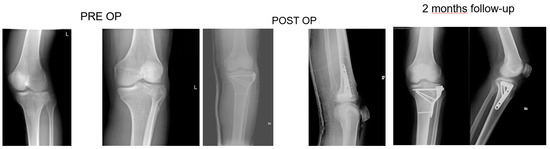

Figure 2. Sixty-year-old patient, X-rays: preoperative, postoperative and control at 6 months follow up of a Shatzker type 3 fracture, AO 41 B 1.3.

All patients had surgery within 48 hours from injury, after administration of spinal or general anaesthesia. A tourniquet was routinely positioned before starting surgical procedure; all patients were operated in a supine position, with injured leg in semi-flexion. Fractures were reduced through a percutaneous or open approach, depending on the cases; SB blocks, which size and shape were customised during surgery considering the features of bone defect for each singular patient, were positioned through a minimally invasive approach via the bony window exploited for reduction; finally, fixation of fracture line and implant were performed with screws and plates (see exemplificative Figure 1, Figure 2 and Figure 3). In one case fixation of the plateau fracture occurred through an arthroscopic approach. All the patients included in the study had identical post-operative regimen. Active knee mobilization and static quadriceps exercises were encouraged from the third day after surgery. Partial weight bearing was allowed at 4–6 weeks after surgery, and progressively increased to achieve full weight bearing at 12 weeks. Prophylaxis for thromboembolic events was obtained through administration of 4000 IU/day of low molecular weight heparin (LMWH) (enoxaparin), until full weight bearing was allowed.

Patients were clinically and radiologically assessed before surgery, at 2 weeks, and then at 1, 2, and 6 months, and 1 year after surgery. Same radiologist carried out the imaging, while evaluations were pooled by different clinicians. Clinical assessment consisted of a visual analogue scale (VAS) for the evaluation of pain, where patients were asked to report the level of pain during the day life activities; measurement of the range of motion (ROM) of the knee joint; and objective examination, intended to highlight possible alterations of surgical scar, vascular and nervous deficits, as well as infectious complications. Moreover, at 1-year follow-up Tegner Lysholm Knee Scoring Scale [21] and International Knee Document Committee 2000 (IKDC 2000) [22] questionnaires were administered during control visits, in order to evaluate patients’ subjective perception of knee function. One year after surgery, patients answered to the Short Form (36) Health Survey (SF-36) questionnaire, which scores the general physical and mental health on the basis of eight scales each ranging from 0 to 100 [23]. Radiological assessment contemplated the acquisition of anteroposterior and lateral projections radiographs at each follow-up. Images were examined in order to evaluate various features of healing process, like callus formation and maintenance of fracture reduction; as well as to detect the presence of possible malalignment, pseudo-arthrosis, bone non-unions, and articular surface depression or widening (see exemplificative Figure 1, Figure 2 and Figure 3).

At six months, X-rays images showed that all 34 fractures displayed a good consolidation rate, as confirmed by radiological reports. In particular, radiolucency of the xenografts was assessed [20], which became progressively more similar to that of the surrounding healthy bone tissue (see exemplificative Figure 1, Figure 2 and Figure 3 and comparative images in Figure 4).

Comparison with the current literature is challenging, due to the lack of standardised follow-up protocols and differences in quantitative assessment of outcomes among the studies. However, the implant of SB in our series resulted in a standard return to knee mobilisation, as highlighted by the mean ROM at last follow-up and the return to partial weight bearing at 4–6 weeks. We also described no complications, like infections and joint subsidence, if compared to similar studies present in the medical literature [31]. Radiological follow-up did not show diastasis or depressions of tibial articular surface excluding the incomplete subchondral reductions documented at the first post op X-ray, which means that mechanical properties of SB were adequate for high and complex forces which the plateau commonly undergoes. At each follow-up, the radiolucency of implants was progressively more similar to radiolucency of the surrounding bone (see exemplificative Figure 1 and Figure 2). We interpreted this evidence as supporting the thesis that SB would have been able to integrate with autologous bone tissue, favouring deposition of new bone matrix within an ongoing remodelling process: indeed, there is a clear morphological pattern on the evolution of the standard X-Ray imaging series over time which shows the substitution of the grafted material with a more homogeneous signal in the area of graft implant. As already demonstrated, the progressive remodelling together with an increase of the mineral signal cannot be dependent on the active remodelling of the graft per se given it is a decellularized matrix. Therefore, the increase in the density over time depends on novel mineral matrix apposition likely induced by the graft, as previously shown both in vivo and in vitro [7,20].